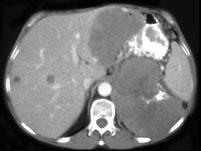

问题 女,38岁,低热乏力并消瘦2个月余,CT如图所示,下列说法正确的是 ( )

选项 A、肺内多发小结节病灶,考虑为肺转移瘤 B、肺内多发小结节病灶,考虑为肺结核 C、左侧肾上腺区巨大的占位性病灶考虑为嗜铬细胞瘤 D、左侧肾上腺区巨大的占位性病灶考虑为肾上腺腺瘤 E、左侧肾上腺区巨大的占位性病灶考虑为肾上腺癌

答案 AE